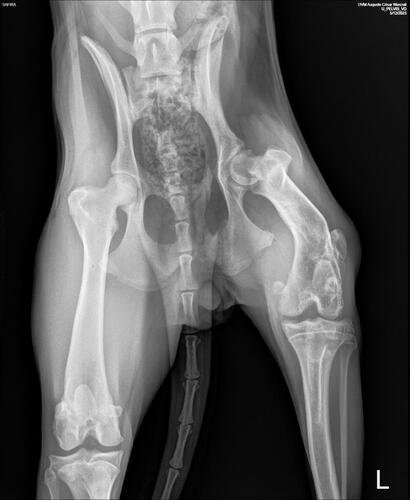

Como era filhote, Safira cresceu com a perna quebrada, fazendo com que o seu osso calcificasse da maneira errada, implicando diretamente no encurtamento da sua perna traseira. Além da perna quebrada, foi descoberto também que Safira possui um "corpo estranho", possível tumor, na mesma perna.

Safira já fez exame de sangue e raio x, agora precisa passar por outros procedimentos, como:AnestesiaBiopsiaRetirada de fragmento (possível tumor)

Esse será o primeiro passo do tratamento. Safira ainda vai passar por uma cirurgia ortopédica para tratar da perna quebrada, porém não temos ainda um orçamento, visto que é necessário os primeiros cuidados (procedimentos citados acima).